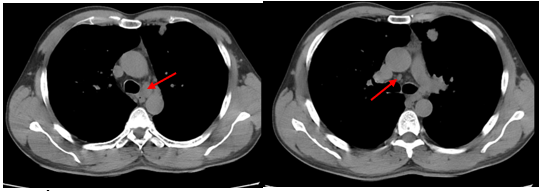

-         CT ổ bụng:

Hình 3. Trên phim chụp CT ổ bụng: Nhu mô gan sát bao gan phân thùy S5 có nốt giảm tỷ trọng trước tiêm, ngấm thuốc kém sau tiêm, đường kính 10mm – Theo dõi tổn thương thứ phát. Dày tuyến thượng thận trái.

Trên phim chụp cắt lớp vi tính ổ bụng:

Trước điều trị:

Sau 3 tháng điều trị: Tổn thương gan và thượng thận đã biến mất.

Hiện tại trong quá trình theo dõi gan và thượng thận 2 bên vẫn chưa xuất hiện tổn thương mới.